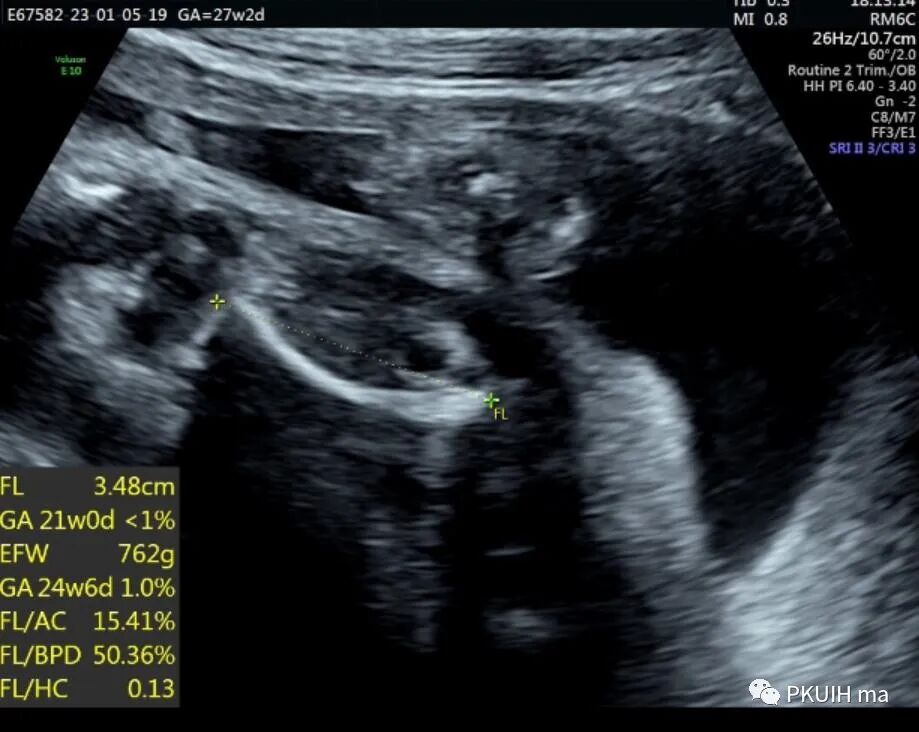

孕妇26岁,G2P0,发现胎儿肢体异常来诊,目前孕27周,超声图像如下:

四肢长骨均短缩、弯曲成角,Z值小于-4,孕妇自述第一胎也是肢体明显短,最后在当地医院引产,未做其他相关检查,本次怀孕又发现胎儿肢体短,因此来京咨询并做相关检查。

产前诊断主要依靠超声或核磁,出生后主要依靠X线和螺旋CT。超声检查建议采用连续顺序追踪法来观察胎儿肢体,如果怀疑有骨骼疾病应进行完整的胎儿超声评估,包括胎儿胎儿运动的评估。当有骨骼发育不全家族史时,应对以下超声征象仔细评估:完整的生物学测量,包括BPD、HC、AC,所有长骨的长度,股骨/足底比值,和下颌骨、锁骨、肩胛骨、颅骨、胸廓和脊柱的观察或测量。其他可能有助于鉴别骨骼发育不良的超声参数包括胎儿面部轮廓(比如鼻骨扁平)、椎体是否存在及形状、手和足的外观(比如多指(趾)、缺指(趾)或指(趾)畸形)和用来评估致死性风险的胎儿胸部。有研究显示FL/AC比值小于0.16是致死性骨骼发育不良胎儿的主要鉴别要点,并且该测值比股骨短、胸围、胸围/腹围更有效。